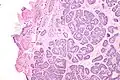

Micrograph of a Sertoli cell nodule. H&E stain. -

Sertoli cell nodules are unencapsulated nodules that consist of:[2][3][4]

- cells arranged in well-formed tubules (that vaguely resemble immature Sertoli cells), with

- bland hyperchromatic oval/round nuclei that are stratified, and

- may contain eosinophilic (hyaline) blob in lumen (centre).